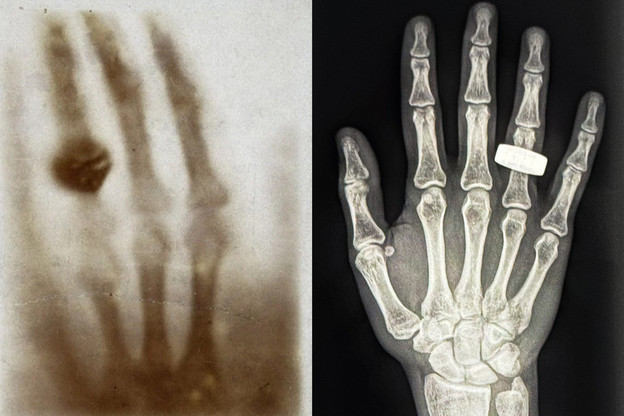

Slika lijevo je prva medicinska rendgenska slika ikad snimljena prije 130 godina, uz prvu rendgensku sliku snimljenu u svemiru (desno), koja prikazuje ruku astronauta s prstenom.

Prošli tjedan članovi posade misije Fram2 objavili su na društvenim mrežama i podijelili prvu medicinsku rendgensku sliku snimljenu u svemiru. Slika je crno-bijelo skeniranje ruke s prstenom, što je nova inačica prve rendgenske slike koju je prije 130 godina snimio fizičar Wilhelm Roentgen, ruke njegove supruge.

Nova rendgenska slika snimljena je u mikrogravitaciji, unutar svemirske kapsule za četiri osobe koja leti orbitalnim brzinama od 44.256 km/h.